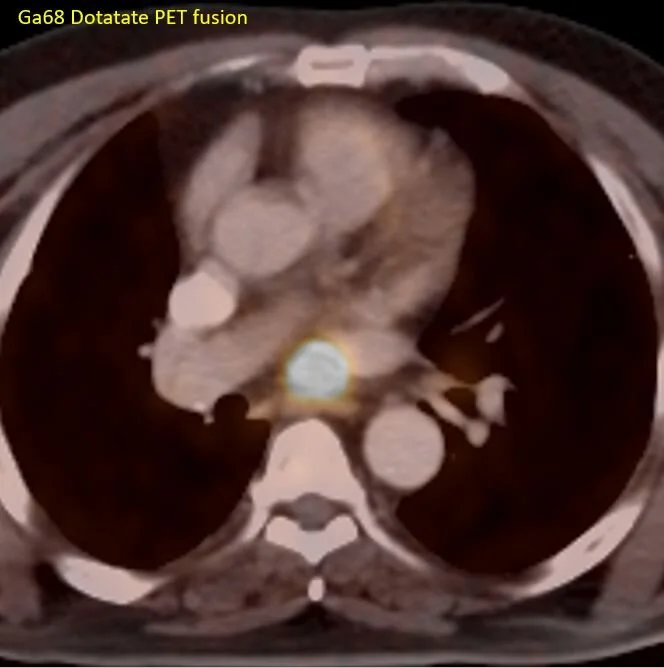

Spectral CT gives a clue. The nodule is intensely enhancing, with very high iodine uptake. Combined with the location of the nodule in the roof of the left atrium, a cardiac paraganglioma was suspected. A gallium 68 dotatate scan performed, which shows intense uptake in this nodule, confirming the diagnosis.

Dotatate scan: The nodule shows uptake, consistent with neuroendocrine tumor. Note physiologic uptake in the spleen, adrenals and kidneys, as well as uncinate process of pancreas.

Fusion image confirms uptake in the subcarinal nodule.